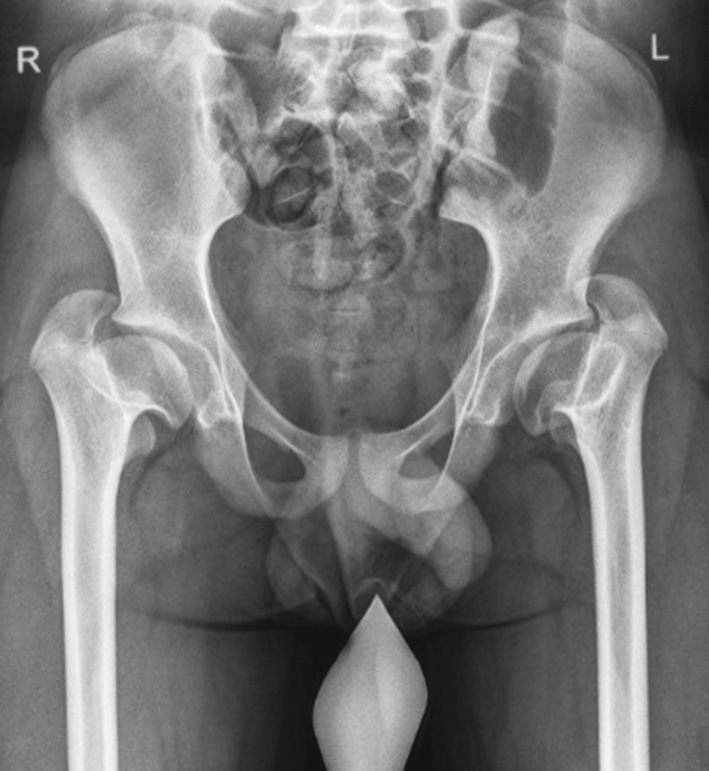

- effects of hematogenous osteomyelitis (septic arthritis) in 101 (28.9%) of all patients. These 101 patients included those who had been exposed to intrauterine infections and those who underwent surgical interventions in the first year of life for congenital heart defects, esophageal atresia, intestinal obstruction, and tracheoesophageal fistula, all complicated by infection of the hip joints (Fig. 4);

Fig. 4. Radiographs of patient J. at the age of 7 years: frontal view (a) and Lauenstein view (b). Hematogenous osteomyelitis resulted in multiplanar deformity of the proximal femur with a high position of the greater trochanter on the left